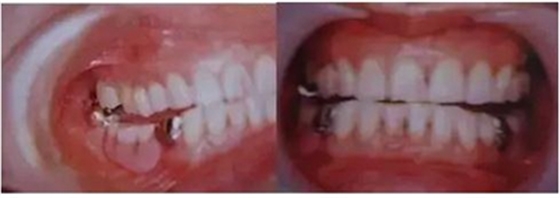

圖9. 上頜和下頜第二磨牙中發(fā)生的前方誘導(dǎo)干擾引發(fā)的張口困難。

下頜磨牙的遠(yuǎn)中頰側(cè)牙尖的近中頰側(cè)斜面和上頜磨牙的近中頰側(cè)牙尖的遠(yuǎn)中腭側(cè)斜面相接觸。

圖10. 不考慮下頜第三磨牙的咬合平面破壞的修復(fù)體制作完成后

后方磨牙干擾引發(fā)的前方誘導(dǎo)干擾。